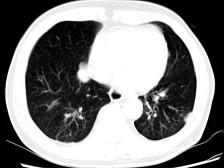

问题 男,64岁,咳嗽半月,咯血一天,不发热,结合影像图像选择最可能的诊断 ( )

选项 A、结节病 B、组织胞浆菌病 C、肺转移性瘤 D、肺结核 E、金葡菌肺炎

答案 C